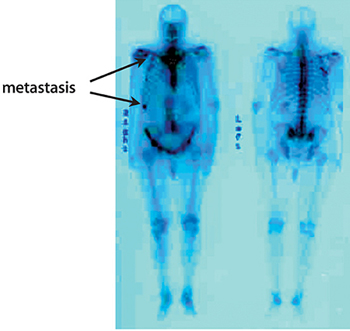

Gammagrafía ósea. Es una prueba que nos permite detectar si el tumor ha invadido los huesos. Se realiza inyectando un isótopo radiactivo en la vena que se fija en las zonas donde el hueso esta dañado. Una cámara especial detecta los acúmulos de radiactividad y forma una imagen de todo el esqueleto. Estos acúmulos también aparecen en casos de lesiones inflamatorias (artritis), antiguos traumatismos u otras patologías óseas.